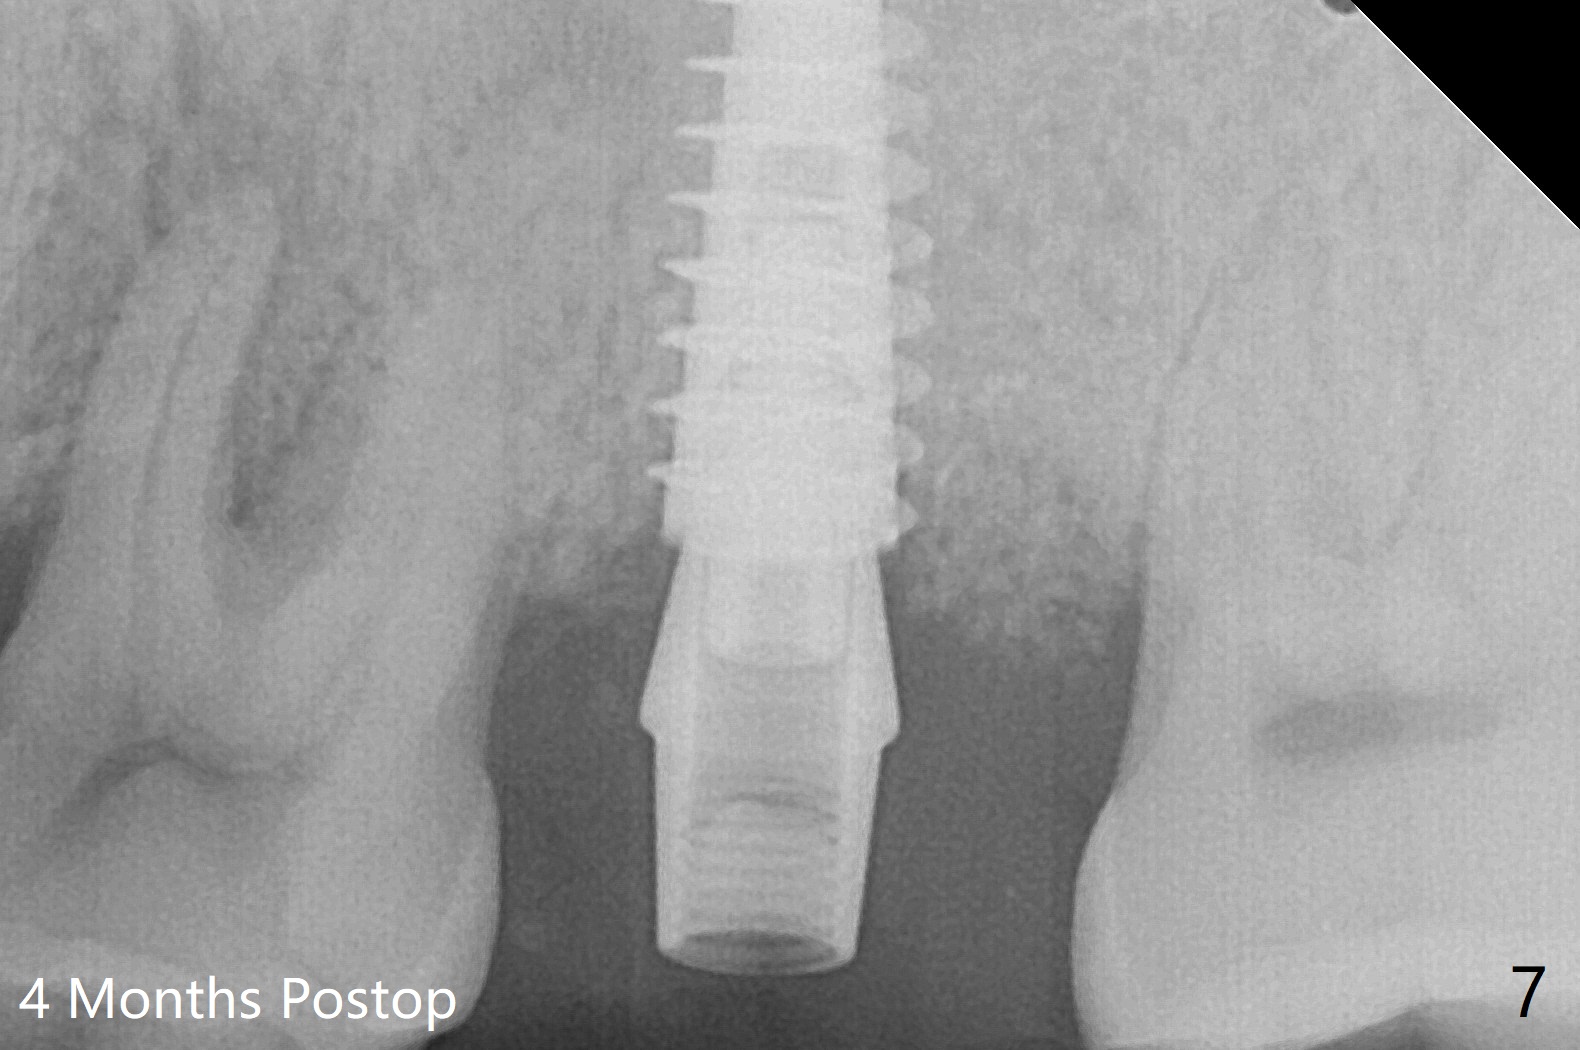

At #15, the sinus floor is initially perforated with modified drill sequence. With placement of PRF and bone graft in the osteotomy, the same 4.5x11 mm dummy implant is inserted to start sinus lift (Fig.4 *). When the dummy implant is removed, more bone graft is placed into the osteotomy and pushed into the sinus with the 5x11 mm final implant (Fig.5). Second round of bone graft is placed next to the implant before placing a 4.5x4(2) mm abutment, but the latter appears not to be seated completely, as indicated by the arrowhead. After use of 6 mm profile drill, a 4.5x4(3 (cuff)) mm abutment is able to be seated apparently completely without a gap (Fig.6 <). The third round of bone graft (Fig.6 *) is placed around the abutment to make sure that the underlying implant is fully covered to reduce periimplantitis in the future. The bone graft around the abutment disappears most coronally, while that around the implant remains 4 months postop (Fig.7). The implant is stable.